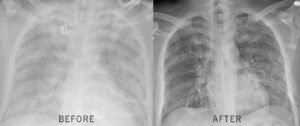

Within 17 days, the stuntman went from planning his funeral to riding 12 miles on horseback. His FEV1 jumped 31%. The rapper went from cutting sessions short to recording for hours—no inhaler needed.